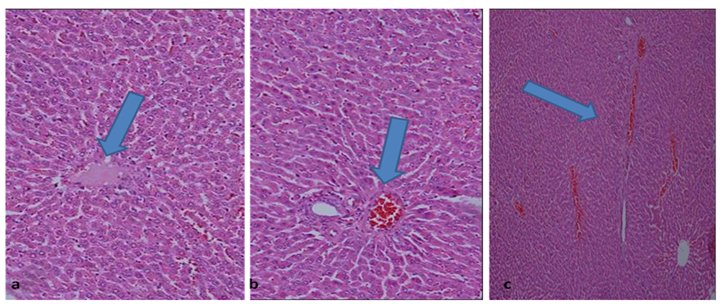

Fig.6: Photomicrographs of liver parenchyma from (a, b) male rats and (c) female rats (subcutaneously injected) with PEG-gold NRs for six months showing normal hepatocytes around the central vein and the portal tract with minimal congestion and inflammation in portal tracts (Hx&E. X200, 100)

In the chronic toxicity study

Microscopic examination of rat's liver injected IV or SC or IM with PEG-gold NRs for six months showed normal hepatocytes with minimal hemorrhage and inflammation around blood vessels. No significant difference between male and female in the hepatic architecture (fig. 6).